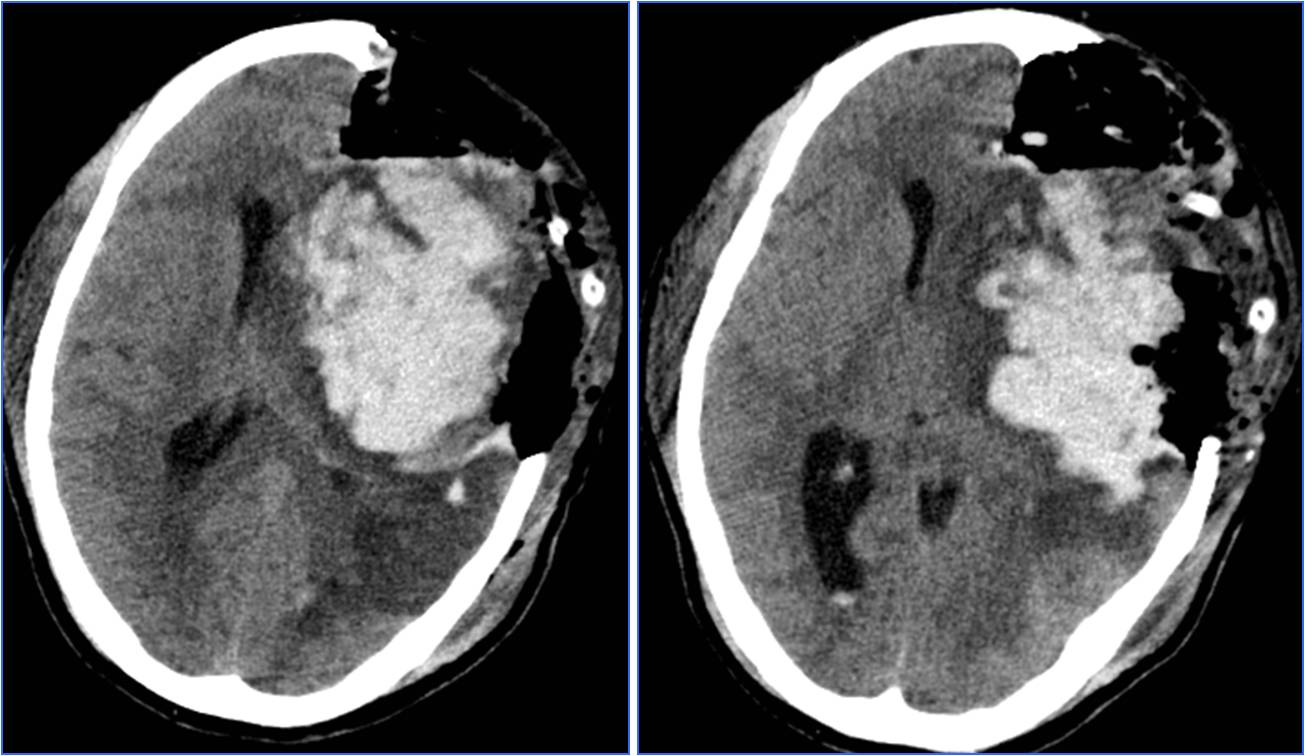

Case8 风心病、心脏瓣膜病脑栓塞

》58岁,女性,既往风心病、房颤、心脏瓣膜病

》因“活动后心慌胸闷5年”于心外科住院,拟行心脏瓣膜置换术

》12:30出现言语不清、左侧肢体无力,NIHSS 18分

》13:00完成头CT检查

》请神经内科会诊,转科 Ø14:00行股动脉穿刺

》15:15结束手术

》16天后出院,NIHSS 2分

再发脑栓塞

》6月份行二尖瓣、主动脉瓣置换术

》7:50出现言语不清、左侧肢体无力,NIHSS 25分

》9:10完成头CT检查

》9:35行股动脉穿刺

》10:05结束手术

》10天后出院,NIHSS 3分

》原因:服用华法林不达标,INR 1.31

Case9 房间隔缺损脑栓塞

》女,29岁,既往健康

》8:10突发言语不清、右侧肢体无力

》9:05分到达急诊科,NIHSS 10分

》9:26完成头MRA检查

》10:35行股动脉穿刺

》10:58血流重建 11天后出院,NIHSS 0分

▼术前头MRA

▼术后24小时CT

》查找病因

》TCD发泡试验提示右向左固有型大分流

》经食道超声提示房间隔缺损大小约8mm

》转心外科行微创房间隔缺损封堵术

Case10 不明原因脑栓塞

》女,43岁。既往健康。

》15:30突发言语不清、右侧肢体无力

》16:30分到达急诊科,NIHSS 22分

》16:44完成头CT检查

》16:55阿替普酶静脉溶栓

》18:17行股动脉穿刺

》18:53血流重建

》12天后出院,NIHSS 0分

▼术后24小时头MRA